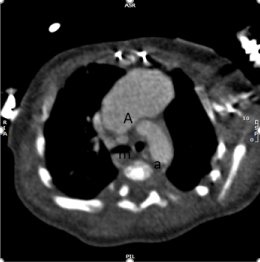

A child with history of tricuspid valve atresia, ventricular septal defect and interrupted aortic arch who underwent initial single ventricle palliation with Norwood procedure, modified Blalock Taussig (BT) shunt placement, and aortic arch repair at age of 11 days. His course was complicated by concerning finding for aneurysm on routine follow up echocardiogram. He had cardiac computed tomography (CT) imaging at age of 2 months. The cardiac CT showed giant aneurysm in the region of modified Blalock Taussig shunt that extends to anterior mediastinum (Figure 1-3). The patient was managed conservatively. At the time of the second palliative surgery, bidirectional Glenn procedure, at age of 7 months, the fibrosed tissue of pseudoaneurysm was resected. Subsequently the patient underwent fenestrated fontan procedure without any complication at age of 3 years and 9 months. He did well after his Fontan procedure.

Figure 1A. Cardiac CT reconstructed image in axial view: A: aneurysm, m: proximal modified Blalock Tausig shunt, a: aortic arch